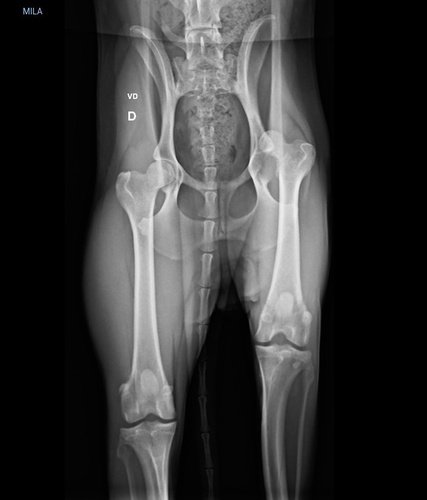

Essa é a Mila, ela foi encontrada abandonada em Janeiro de 2024 com a patinha traseira machucada. Para que ela possa voltar a andar normalmente, é necessário fazer uma cirurgia chamada colocefalectomia. Mesmo com os descontos concedidos por um veterinário de uma ONG, ainda precisamos de ajuda para melhorar a qualidade de vida dessa cachorrinha. Você pode nos ajudar?